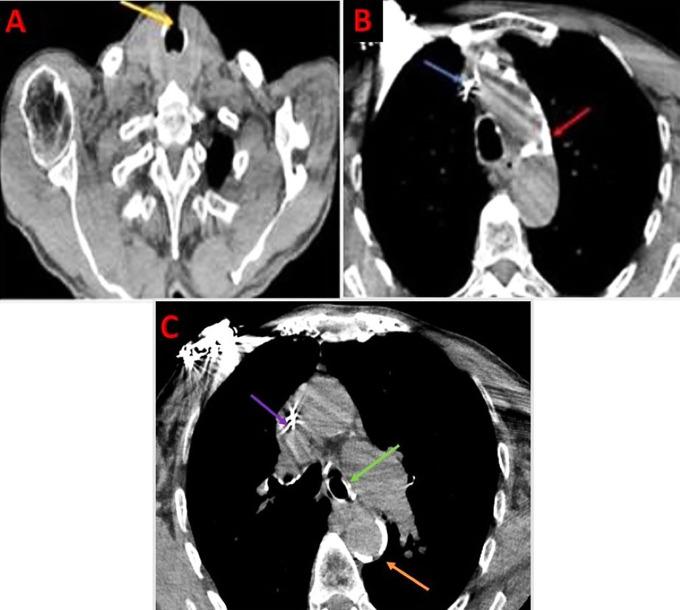

Tracheostomy tube migration is a rare but potentially life-threatening complication. We present the case of a 66-year-old male with chronic obstructive pulmonary disease, dual-chamber pacemaker implantation for chronic ischemic cardiomyopathy, and supraglottic squamous cell carcinoma. The patient developed respiratory distress due to intrabronchial migration of the tracheostomy tube. Initial evaluation revealed significant respiratory effort, inspiratory stridor, and an absent tube at the stoma site. Imaging and bronchoscopy confirmed the tube's presence in the left main bronchus with associated mucosal inflammation. The patient underwent bronchoscopic-guided tube removal and successful repositioning of a cuffed tracheostomy tube under spontaneous ventilation anaesthesia. Following stabilization, he was discharged with plans for a permanent tracheostomy. Tracheostomy tube migration presents a significant diagnostic and therapeutic challenge, particularly given the scarcity of studies involving adults with this complication. This case highlights the importance of early recognition, prompt imaging-especially bronchoscopy-and tailored management strategies, while emphasizing the active involvement of the patient and family in the care pathway. It also underscores the necessity for vigilant monitoring to prevent severe, potentially fatal, complications.

气管造口管移位是一种罕见但可能危及生命的并发症。我们报告一例66岁男性患者,患有慢性阻塞性肺疾病,因慢性缺血性心肌病植入双腔起搏器,并患有声门上鳞状细胞癌。该患者因气管造口管支气管内移位而出现呼吸窘迫。初步评估显示呼吸费力明显、吸气性喘鸣,且造口部位无导管。影像学检查和支气管镜检查证实导管位于左主支气管并伴有相关黏膜炎症。患者在自主通气麻醉下接受了支气管镜引导下的导管取出术,并成功重新放置了带套囊的气管造口管。病情稳定后,他出院了,并计划进行永久性气管造口术。气管造口管移位带来了重大的诊断和治疗挑战,尤其是考虑到涉及该并发症成人患者的研究较少。本病例强调了早期识别、及时进行影像学检查(尤其是支气管镜检查)以及制定个性化管理策略的重要性,同时强调患者及其家属在护理过程中的积极参与。它还强调了 vigilant monitoring to prevent severe, potentially fatal, complications.(此处原文有误,推测可能是“vigilant monitoring to prevent severe, potentially fatal, complications”,直译为“警惕监测以预防严重的、可能致命的并发症”)对预防严重的、可能致命的并发症进行密切监测的必要性。